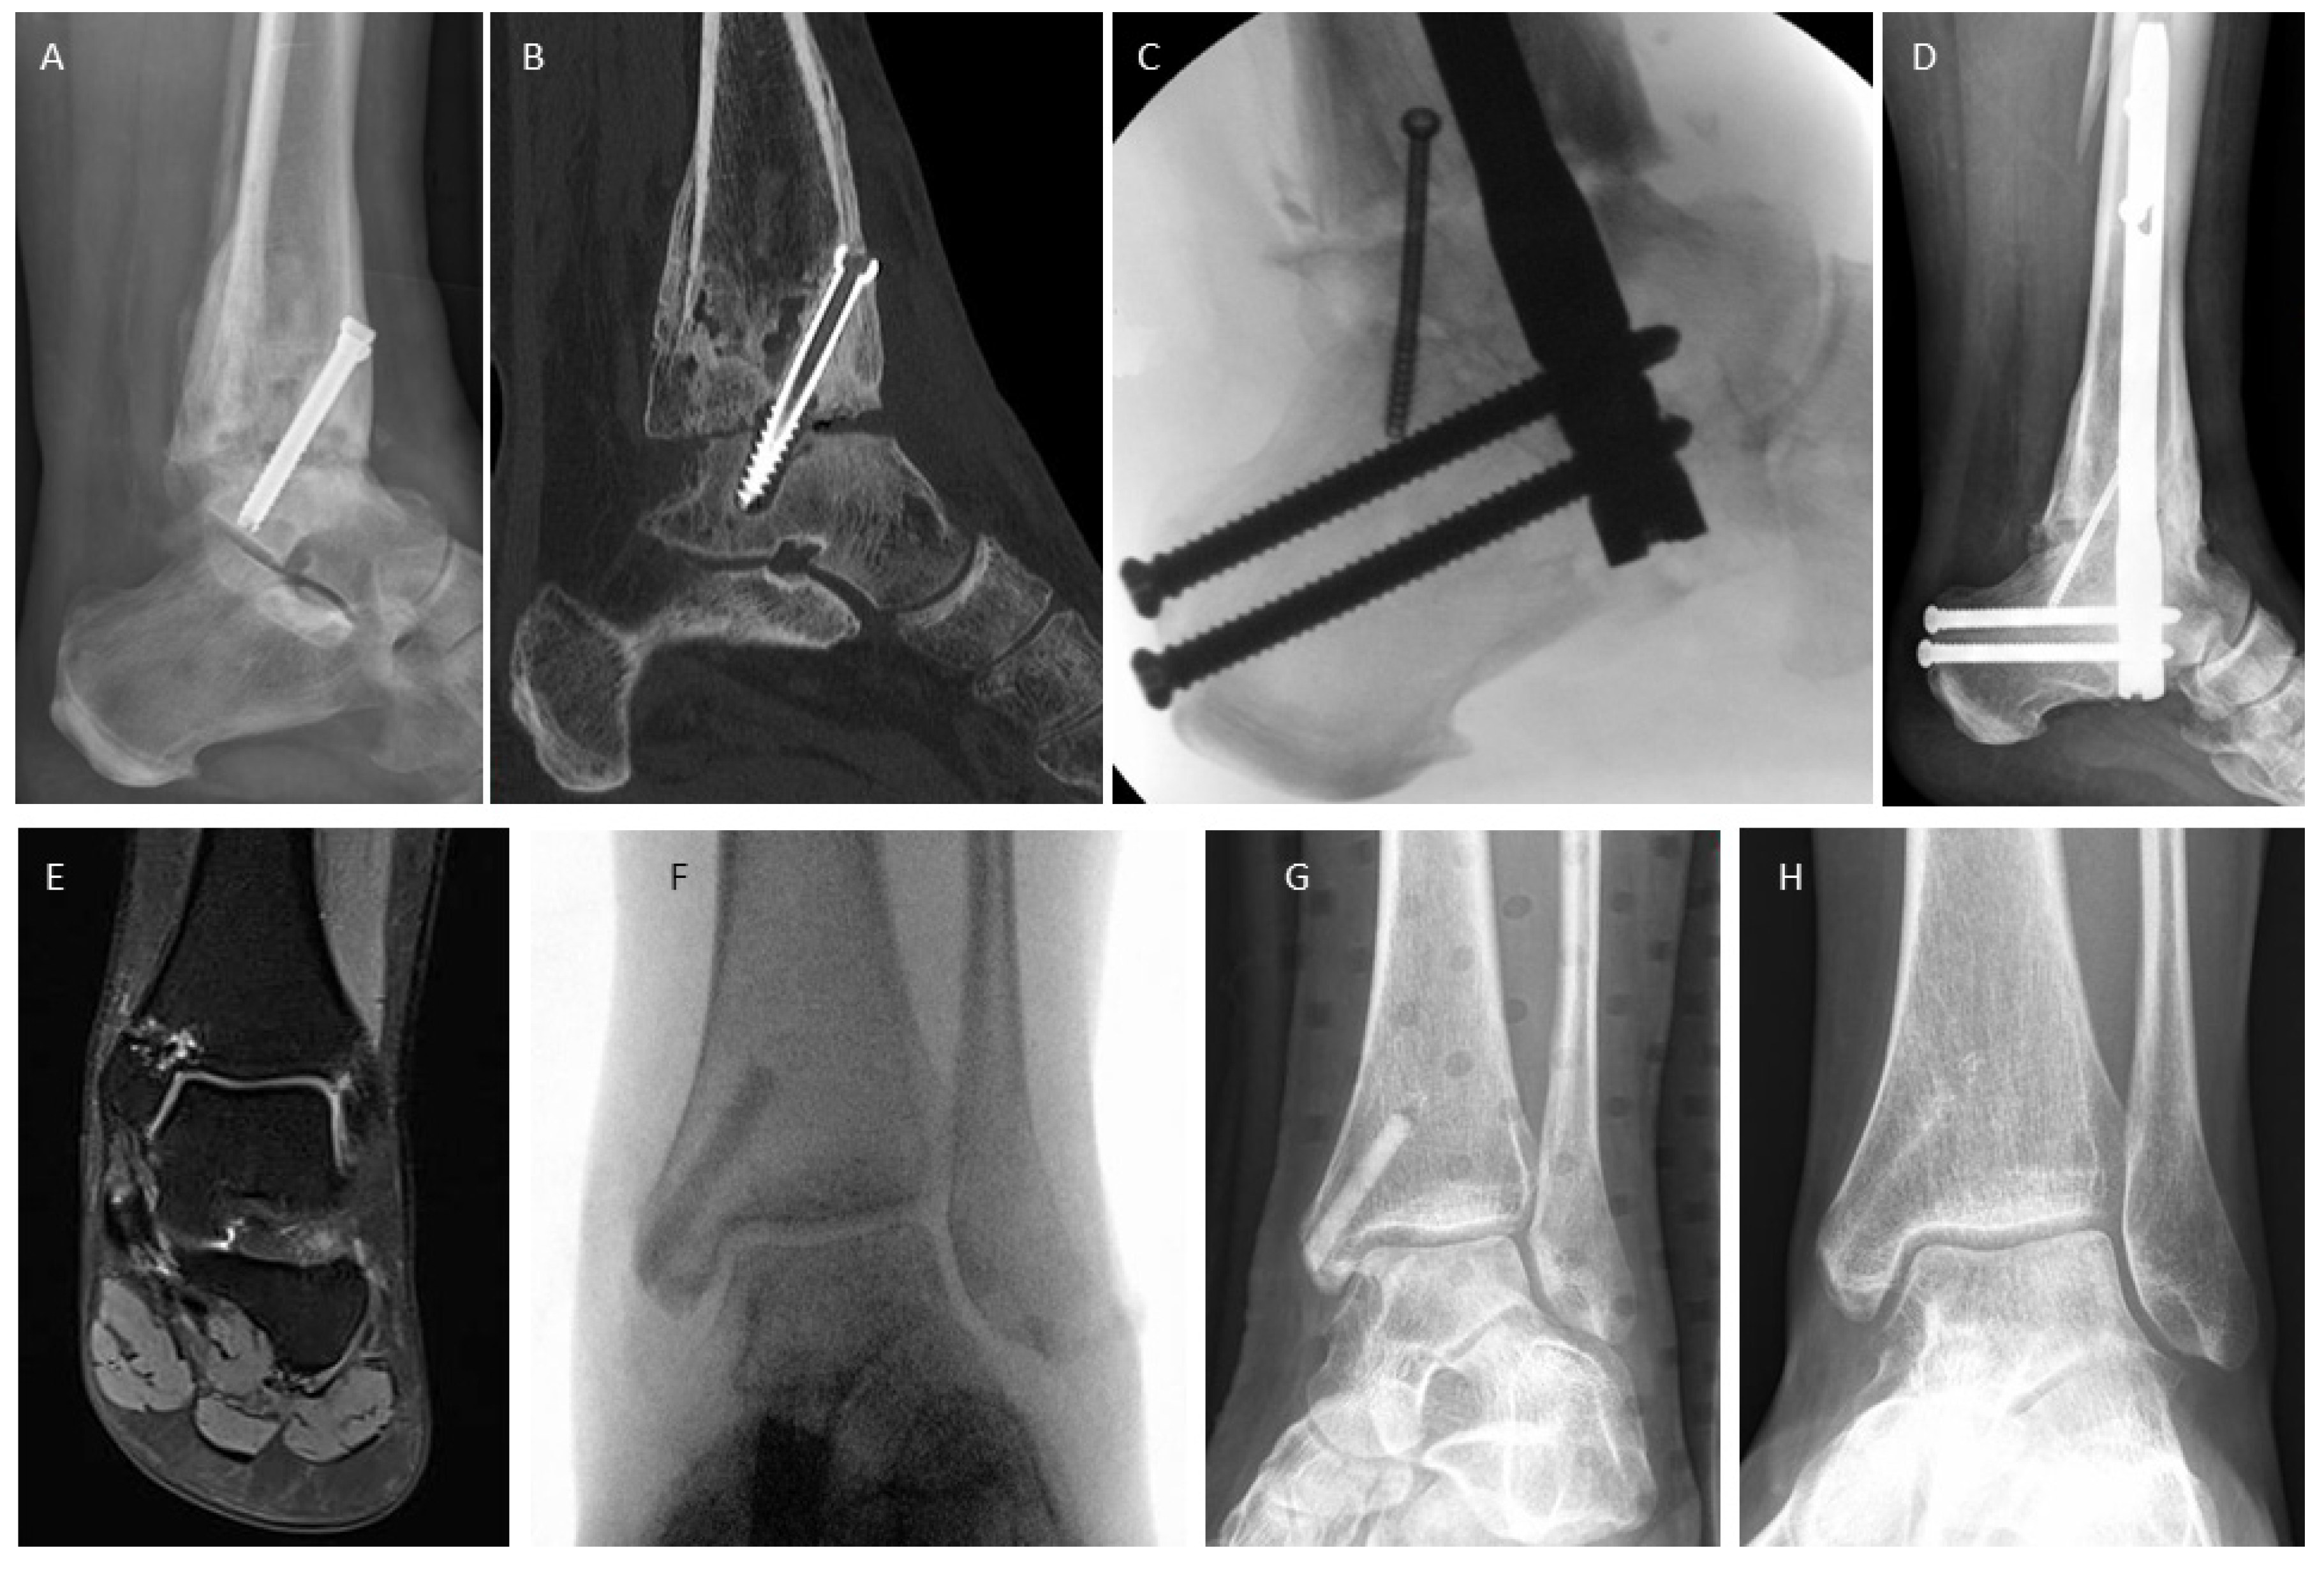

3.4. Examples for Bone Healing

3.5. Clinical Complications

3.6. Radiological Findings of Interest